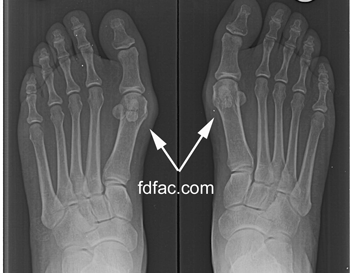

I recently helped a modern dancer who was experiencing bunion pain whenever she danced barefoot — which was all the time. Although her bunions were significantly enlarged, she was pain free as long as she wore shoes.